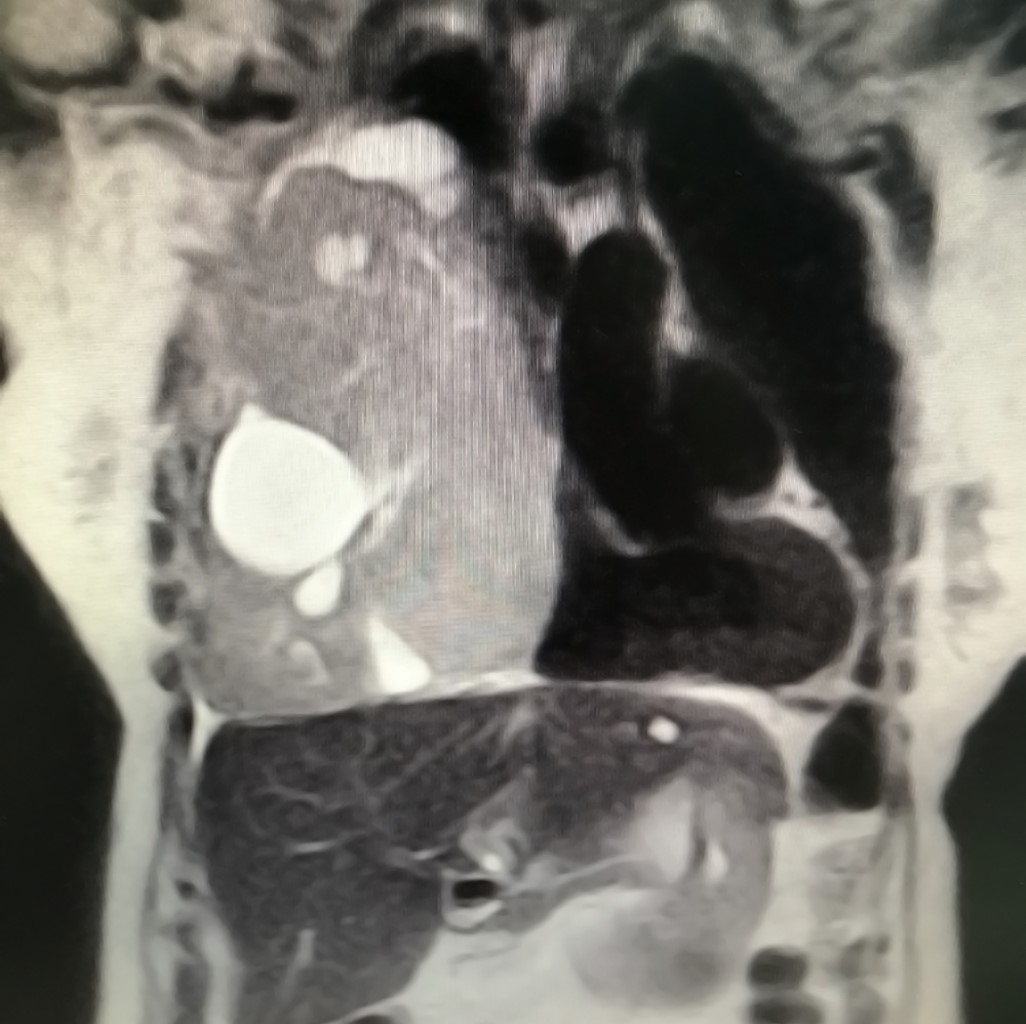

Paciente femenina de 78 años, con antecedente de artritis reumatoide, consulta por disnea progresiva de dos meses de evolución asociado con astenia. Al examen físico se objetiva abolición de murmullo vesicular en campo pulmonar inferior, medio y parte del superior; además de tener espirometría con patrón restrictivo severo. Se solicita tomografía computarizada de tórax (TC) (Figura 1), en la cual se observa masa voluminosa heterogénea, con áreas quísticas, en pulmón derecho, de 126 × 166 mm de tamaño, en íntimo contacto con pared torácica, diafragma y estructuras mediastinales.

Figura 1